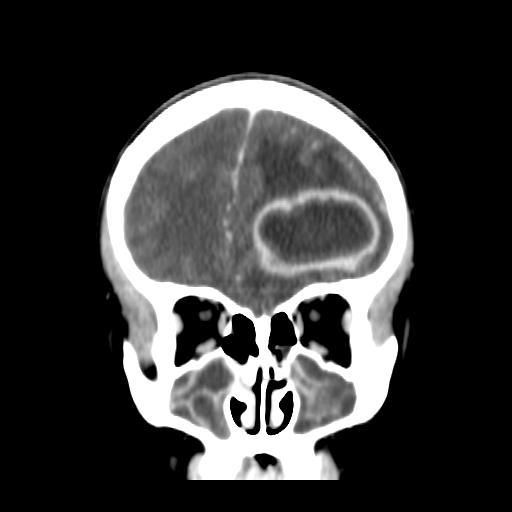

Valorizzando la bradicardia e la persistenza della cefalea, viene eseguita una TAC encefalo che mostra la presenza di un�ampia lesione in sede frontale sinistra del diametro di 5 cm compatibile con ascesso cerebrale, circondato da importante edema (Figura 1).

Figura 1. Voluminosa formazione a prevalente componente ipodensa centrale, circondata da cercine iperdenso e vallo ipodenso di natura edemigena circostante. Importante effetto compressivo sul corno del ventricolo laterale omolaterale causando deviazione della linea mediana verso destra di circa 9 mm. Si riconosce nei settori di destra la presenza di immagine di discontinuit� della corticale sul versante intracranico a livello del seno frontale a destra.